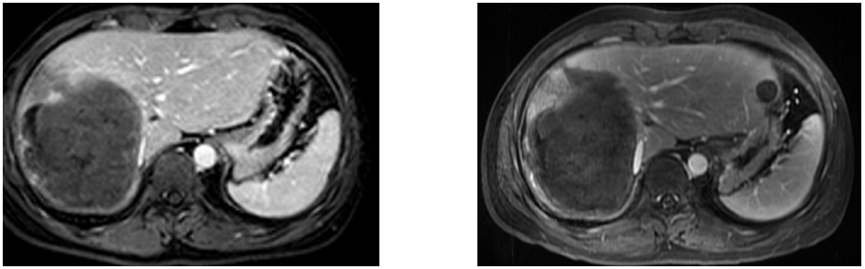

2021年6月11日上腹部MR增强:提示肿瘤较前缩小,内部强化灶较前明显减少,肝左叶代偿性增大。彩超提示肿瘤组织大片坏死,瘤内活癌症较前减少(图4)。

图4.2021年6月11日上腹部MR